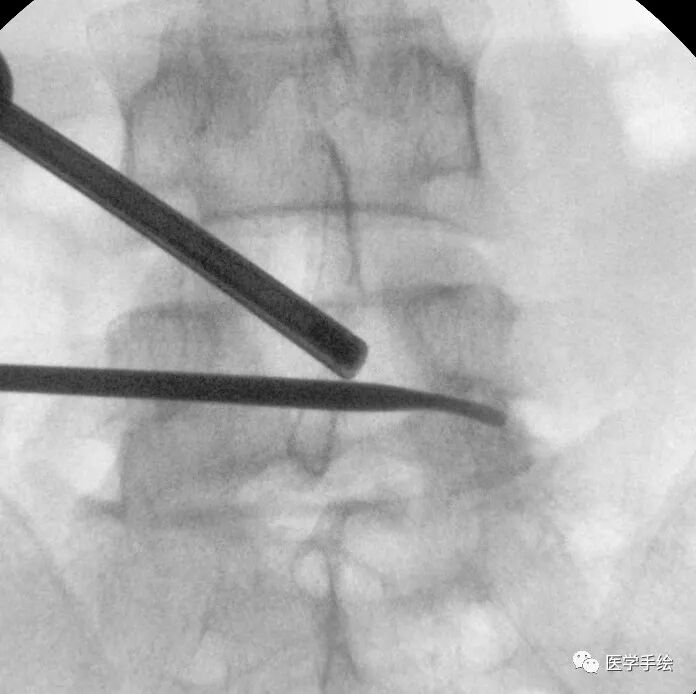

为了避免translamina入路棘突磨穿风险,我们尝试先显露对侧椎板上缘明确对侧椎板方向。

在对侧椎板上缘指示方向下行translamina操作,直至显露对侧黄韧带上缘和椎间孔区域黄韧带

经translamina入路探及下位椎弓孔区域的范围

看到下位椎间孔区域的上关节突尖